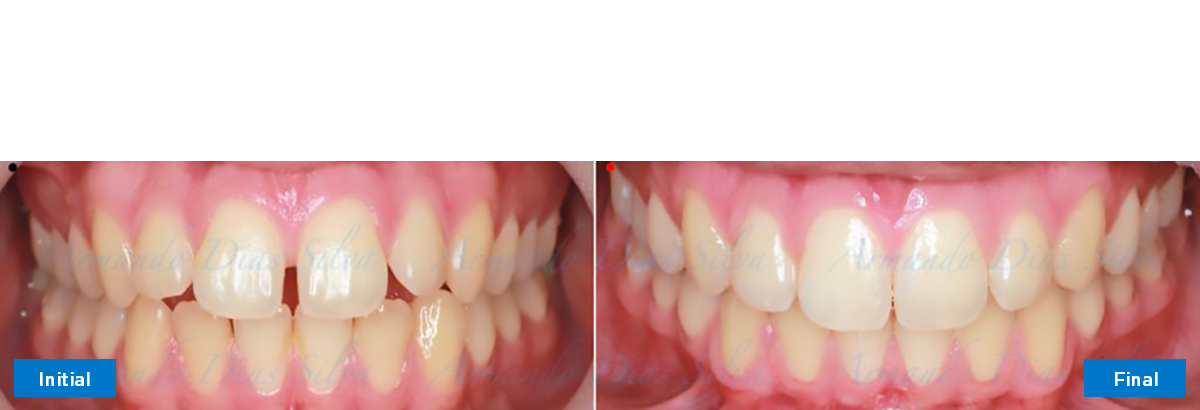

Clase II, Div. 1: Protrusión del incisivo central y espacios anteriores (SureSmile® Aligners)

Principal queja del paciente: Protrusión del incisivo central y mordida abierta. El paciente rechaza la expansión del arco palatino (MARPE) y las extracciones.

Este paciente adolescente presenta molares de Clase II y no le gusta su mordida abierta ni lo protrusivos que son sus dientes frontales. Por sus fotografías faciales, parece que su mandíbula es retrognática o le falta volumen en la barbilla. El historial del paciente también indica que existe un problema funcional al no haber guía de los incisivos.

Se logran todos los objetivos principales:

• Molares de clase I logrados con distalización y sin elásticos

• Sin expansión maxilar, respetando la envoltura periodontal

• Incisivos inferiores retroinclinados, que mejoran la estabilidad a largo plazo

Retención: Arco superior retenido con retenedor transparente. Arco inferior retenido con retenedor lingual unido de canino a canino.